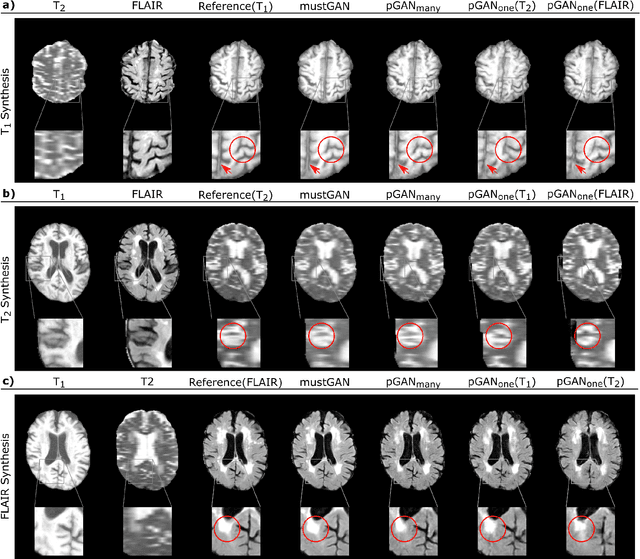

Abstract:Multi-contrast MRI protocols increase the level of morphological information available for diagnosis. Yet, the number and quality of contrasts is limited in practice by various factors including scan time and patient motion. Synthesis of missing or corrupted contrasts can alleviate this limitation to improve clinical utility. Common approaches for multi-contrast MRI involve either one-to-one and many-to-one synthesis methods. One-to-one methods take as input a single source contrast, and they learn a latent representation sensitive to unique features of the source. Meanwhile, many-to-one methods receive multiple distinct sources, and they learn a shared latent representation more sensitive to common features across sources. For enhanced image synthesis, here we propose a multi-stream approach that aggregates information across multiple source images via a mixture of multiple one-to-one streams and a joint many-to-one stream. The shared feature maps generated in the many-to-one stream and the complementary feature maps generated in the one-to-one streams are combined with a fusion block. The location of the fusion block is adaptively modified to maximize task-specific performance. Qualitative and quantitative assessments on T1-, T2-, PD-weighted and FLAIR images clearly demonstrate the superior performance of the proposed method compared to previous state-of-the-art one-to-one and many-to-one methods.